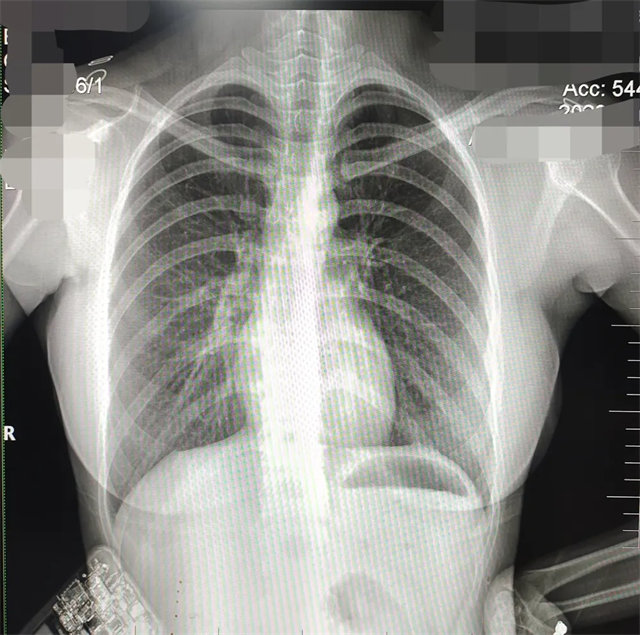

缺陷:肩胛骨未完全拉離肺野,吸氣不完全,存在金屬偽影遮擋,略有聳肩,且肺尖顯示不好,圖像顆粒感較強(qiáng),管電流量不夠,信噪比偏低。

解決:去除金屬物品后,按標(biāo)準(zhǔn)體位,使患者雙肩旋前與前胸一并緊貼成像件,適當(dāng)調(diào)高mAs,然后深吸氣后屏氣曝光。